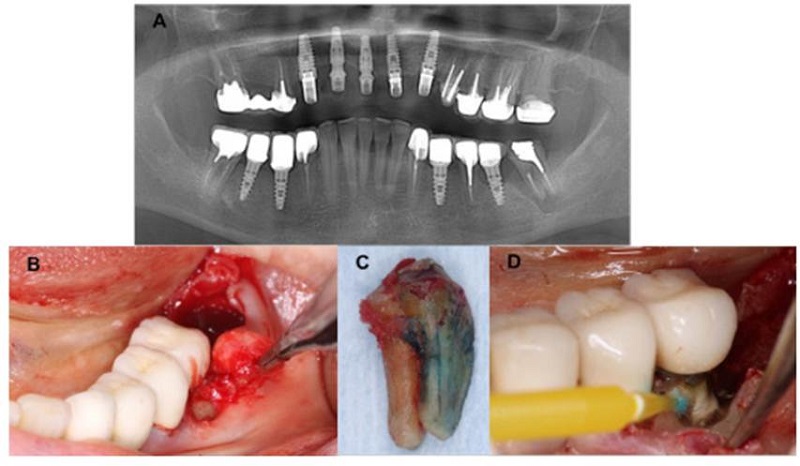

Radiográficamente, se detectó una fractura vertical en la raíz mesial y la presencia de una lesión radiolúcida que afectaba las raíces dentales en el OD 37, tratado antes endodónticamente. Así mismo, se identificó una lesión radiolúcida a nivel del OD 36 (figura 1A). Luego de que el Servicio de Estomatología y Cirugía oral, Endodoncia y Periodoncia evaluó a la mujer, se estableció el diagnóstico de osteomielitis y perimplantitis. Así, se procedió a una exodoncia atraumática del OD 37 (figura 1B). El análisis morfológico del órgano dental extraído permitió constatar una fractura radicular vertical (figura 1C). Antes de proceder a la sutura, fue realizada una preparación y detoxificación perimplantar del od 36 con tetraciclina sumergida en torundas de algodón (figura 1D).